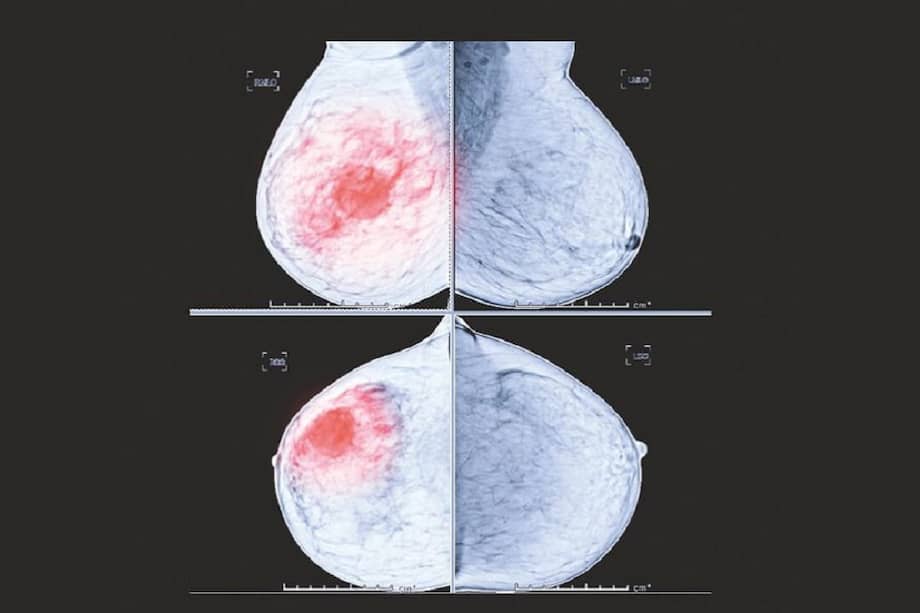

En apenas tres décadas (desde 1990 hasta 2019), la incidencia mundial de tumores entre menores de 50 años ha aumentado un 79%. Además, el número de muertes por cáncer de aparición temprana en 2019 fue de 1,06 millones, un aumento del 27,7% con respecto a 1990. Los principales cánceres de aparición temprana con las tasas más altas de mortalidad fueron los de mama, tráquea, bronquios y pulmón y de estómago. ¿Por qué a los adultos jóvenes les está dando más cáncer?

Un ejemplo es el cáncer de mama: “(…) Descubrimos que el consumo de alcohol y el tabaco siempre fueron los principales factores de riesgo”. La evidencia señala que solo limitar y dejar el alcohol y el tabaco puede servir como una estrategia prometedora para reducir la creciente carga del cáncer de mama de aparición temprana. No es la primera vez que el estilo de vida se asocia como un factor de riesgo para esta enfermedad: la Organización Mundial de la Salud explica que en la actualidad se pueden evitar entre el 30% y el 50% de los casos de cáncer con estrategias como tener una alimentación saludable que incluya frutas y hortalizas, realizar actividad física y evitar el alcohol.